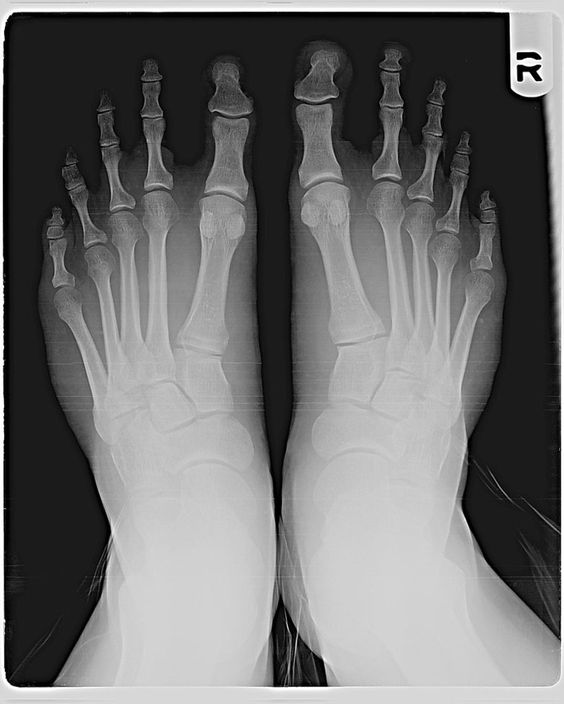

검지발가락이 제일 긴 모양의 발을 ‘그리스인 발'(Greek foot)이라고 한다.

아래 사진은 그리스인 발을 엑스레이로 촬영한 모습이다.